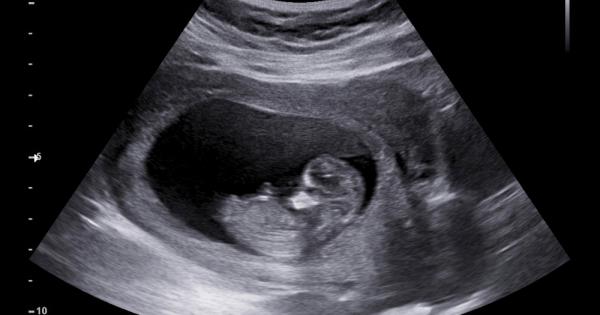

Едно от най смъртоносните състояния на бременността вече може да бъде открито

...... на PAS с 80% точност. Нещо повече – тестът е бил 93% точен при изключването на отрицателния резултат. Изследването е публикувано в Nature Communications. Източник: Science Alert